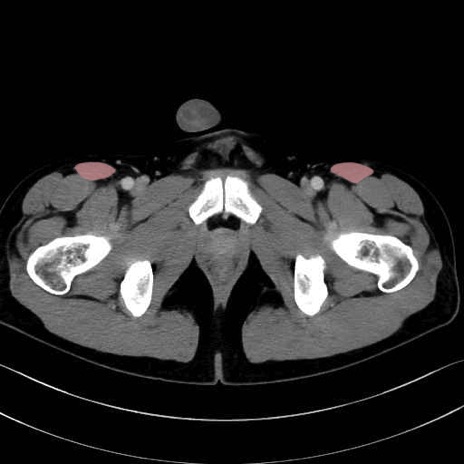

4. 深層外旋六筋(股関節の深部)

内閉鎖筋 (Obturator internus)

外閉鎖筋 (Obturator externus)

大腿方形筋 (Quadratus femoris)